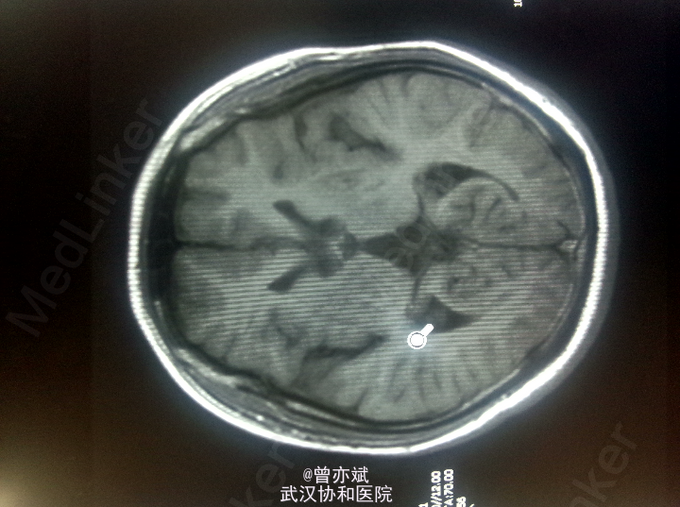

查体:T 36.4℃,P 77次/分,R 20次/分,BP 110/70mmHg。神志清楚,查体合作,皮肤及全身浅表淋巴结未及肿大,心肺腹未及明显异常,双下肢无水肿,生理反射存在,病理反射未引出。 专科查体:神清,吐词不清,语速减慢。双侧角膜可见K-F环,颅神经(-),四肢肌力正常,肌张力减低,左上肢不自主运动,姿势性震颤明显,腱反射对称性活跃,病理征未引出。感觉系统无异常。左手指鼻试验不准。Kernig征阴性。 辅助检查:血常规、尿常规、大便常规、大生化、ENA、ANCA、甲功五项、类风湿三项均阴性,铜蓝蛋白小于20mg/L(正常值220-580mg/L),叶酸、VitB12均正常。MRI平扫+增强 双侧基底节、丘脑、中脑及桥脑、双侧齿状核稍长T1稍高FLAIR信号及双侧苍白球、壳核及黑质信号改变,结合病史考虑肝豆状核变性;脑萎缩,尤以小脑桥脑明显。